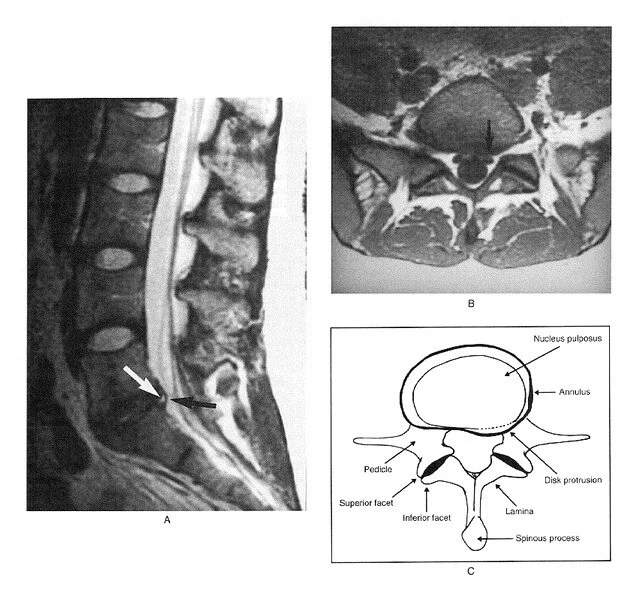

Mild grade 1 (less than 25%) spondylolisthesis (slipping of one vertebra over another). In this case, associated with disc herniation.